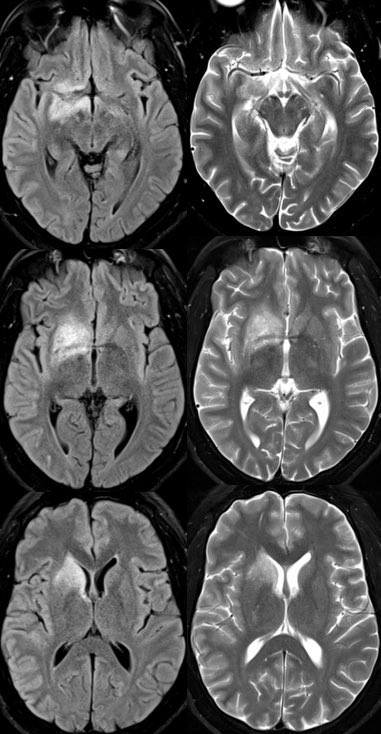

▶️BRAIN findings: Occur in <50% of patients though tend to involve the deep gray matter and infratentorium (particularly in children)

▶️Patterns include ADEM-like or CLIPPERS-like imaging features

▶️Leptomeningeal enhancement can also be seen in association with FUEL & FLAMES x.com

🔷A distinct subtype/clinicoradiographic syndrome of MOGAD is a cortical encephalitis presenting with headache, fever and seizures known as FLAMES of MOGAD🔥

🔷When the predominant imaging features are leptomeningeal enhancement with little to no cortical involvement, this is considered FUEL of MOGAD ⛽️ x.com

▶️Imaging: Unilateral (more common) or b/l cortical swelling (🔥) or isolated leptomeningeal enhancement (⛽️) +/- other features of MOGAD